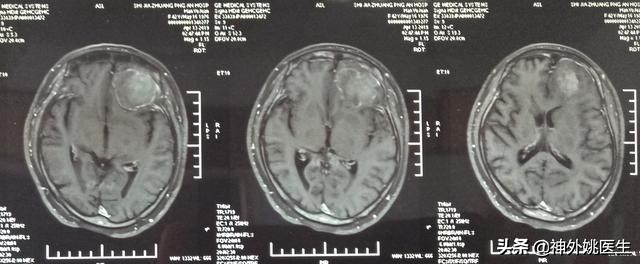

头MRI检查:1、左额部脑膜瘤。2、左侧放射冠区腔隙性脑梗死。(图3-7)

图3 T1像病变呈稍长T1信号。

图4 T1像病变呈稍长T2信号。

图5 T2Flair像病变呈稍高T2信号。

图6 增强扫描可见病变呈不均匀强化。

图7 病变基底位于颅底硬膜,可见脑膜尾征,病变大小约3.8cm x 4.1cm x 2.9cm。